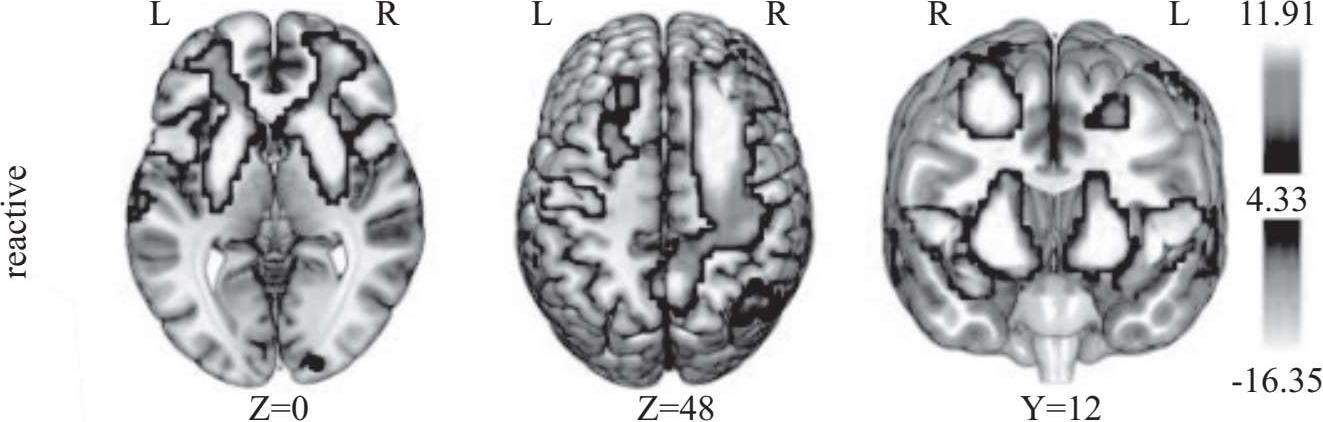

为了更深入地探索这一现象,研究人员运用功能性磁共振成像(MRI)技术对 19 名成年人(25 至 30 岁)和 22 名青少年(13 至 17 岁)的大脑进行扫描。在参与赌博游戏的过程中,研究发现青少年的腹侧纹状体激活程度更高,这一现象即使在两组实验对象面临相同赌注的情况下也依然存在。这表明青少年在追求奖励时更倾向于冒险,以获得更大的回报。这些研究结果表明,青少年大脑对奖励的反应与他们所做出的选择,包括冒险和寻求快乐的行为,直接相关。因此,一些研究人员认为,青少年的这些危险行为可能是由于他们正在发育的大脑中的边缘多巴胺系统过度活跃所驱动的。这解释了为什么青少年更可能尝试诸如酗酒、赌博等高风险行为。

奖励处理过程的研究揭示了奖励预期阶段与体验阶段在神经基础上的分离活动。腹侧纹状体、杏仁核、眶额叶等脑区,以及它们之间形成的神经回路在此过程中发挥着至关重要的作用。对青少年奖励处理过程的脑成像研究指出,青春期的一系列风险行为与大脑区域的发育成熟密切相关。具体来说,负责奖励刺激处理的中脑边缘系统的发育与认知控制的前额叶回路脑区的发展之间存在不平衡的关系。这种不平衡导致了青少年独有的行为特点,包括对奖励的过度反应和冲动控制的不足。这些发现为人们提供了宝贵的视角,以理解和引导青少年在面对各种挑战时的行为选择。通过深入了解青少年大脑的这些特性,人们可以更有效地支持他们的健康成长,帮助他们在关键的青春期做出更明智的决策。

近年来的脑成像研究揭开了奖励处理过程中的一个谜:在奖励预期阶段与结果阶段,大脑神经活动呈现出神经解剖回路的明显分离。特别是在青少年时期,这一时期的主要特征之一是风险寻求行为的显著增加,这表现在奖励相关区域的大脑活动更为频繁,而在规避风险的相关脑区则呈现出较少的神经活动。下面将详细探讨青少年在奖励处理过程中所涉及的主要脑区,包括奖励刺激处理的脑区以及监察风险的脑区,以及这些区域在奖励处理的预期与结果阶段的认知机制和神经活动的变化。通过这一深入分析,人们不仅能够更好地理解青少年的行为和决策模式,而且能够为青少年的心理发展和行为引导提供科学依据。这些脑成像研究的成果不仅对神经科学领域具有重要的科学意义,而且为家长、教育工作者以及心理健康专业人员提供了关于青少年行为背后的生物学基础的宝贵洞见。了解青少年大脑在面对奖励和风险时的反应方式,是帮助他们健康成长和避免潜在风险的关键。